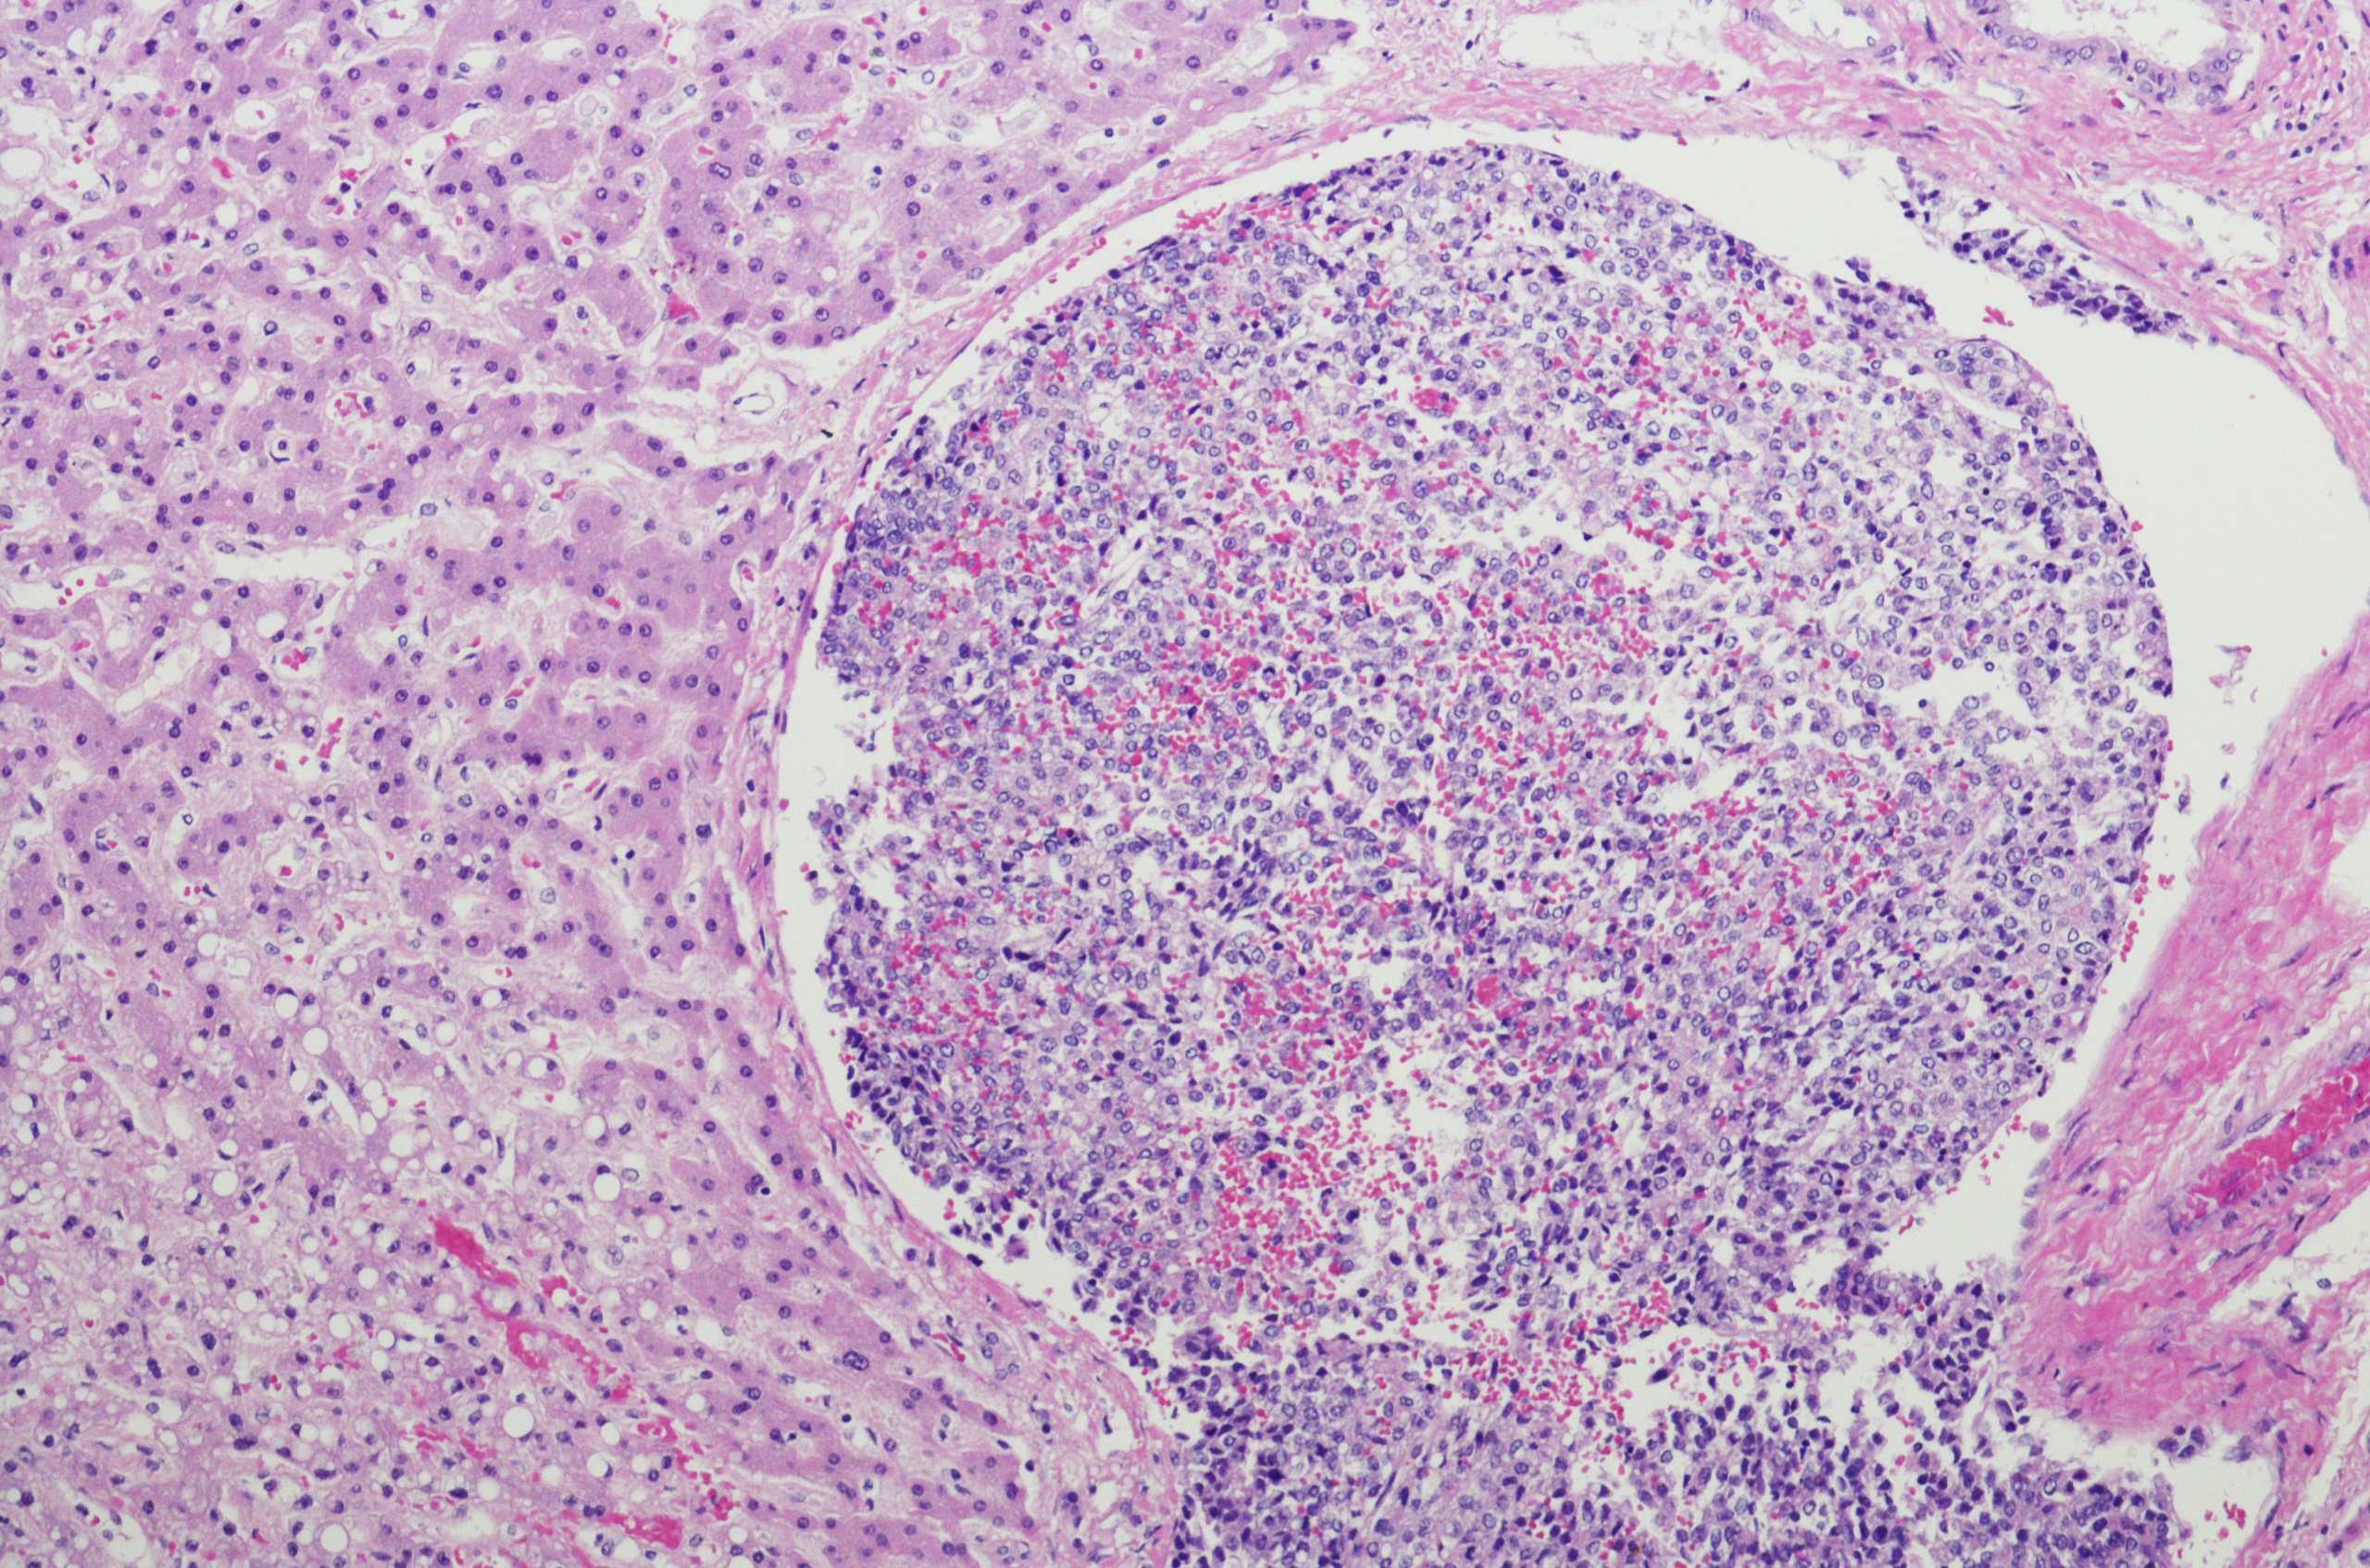

Children’s Liver Tumours

Other Rare Childhood Cancers

Tumours that normally only occur in adults are occasionally found in children and include cancers of the digestive system, the thyroid, and the adrenal gland.